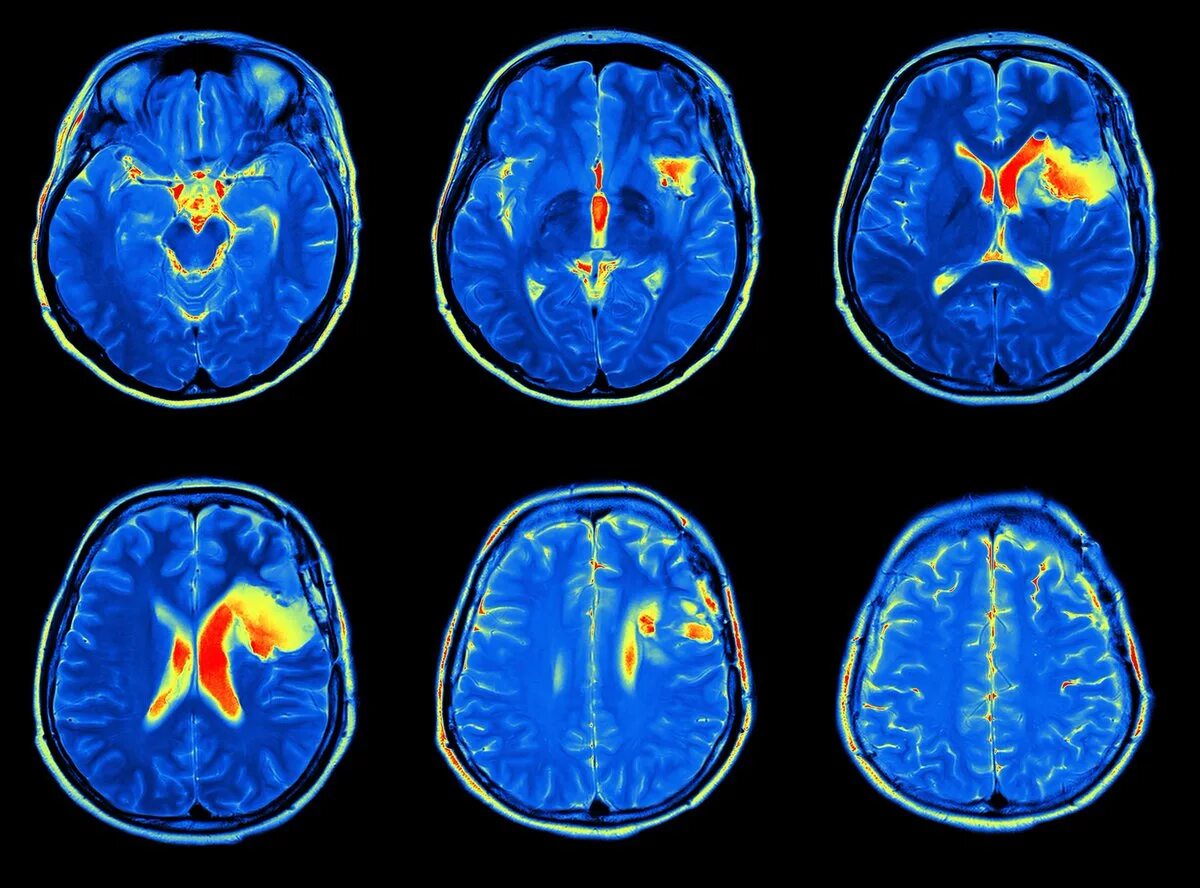

Что покажет мрт головного мозга с контрастом